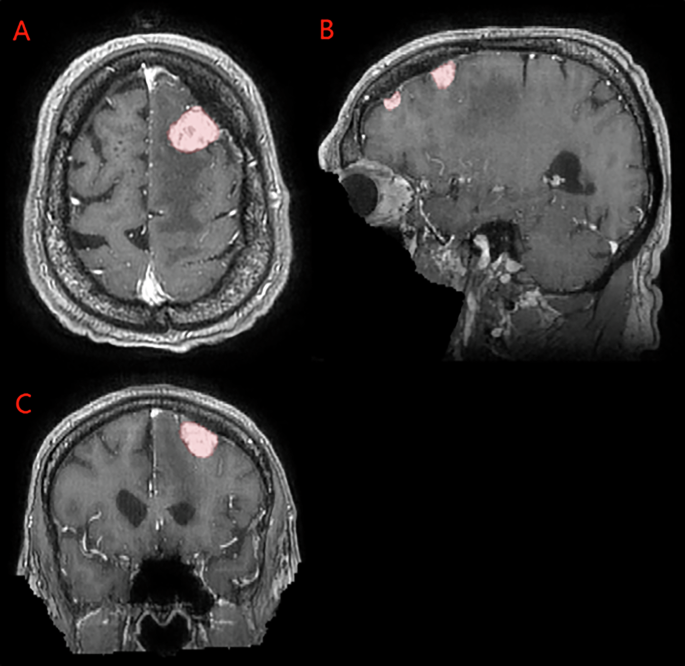

The imaging dataset includes exclusively 3D T1c brain MRI scans in native acquisition resolution in either the intact (Fig. 1) or postoperative setting (Fig. 2, 3), which mimics the data available for most radiotherapy planning. While additional sequences such as T1-weighted, T2-weighted, T2-FLAIR, and computed tomography are sometimes used in clinical workflows, these were not consistently available nor required for RT planning at all centers and were therefore not included in the dataset.

Panels A, B, and C depict two distinct intact meningiomas (red) on axial, sagittal, and coronal images respectively.